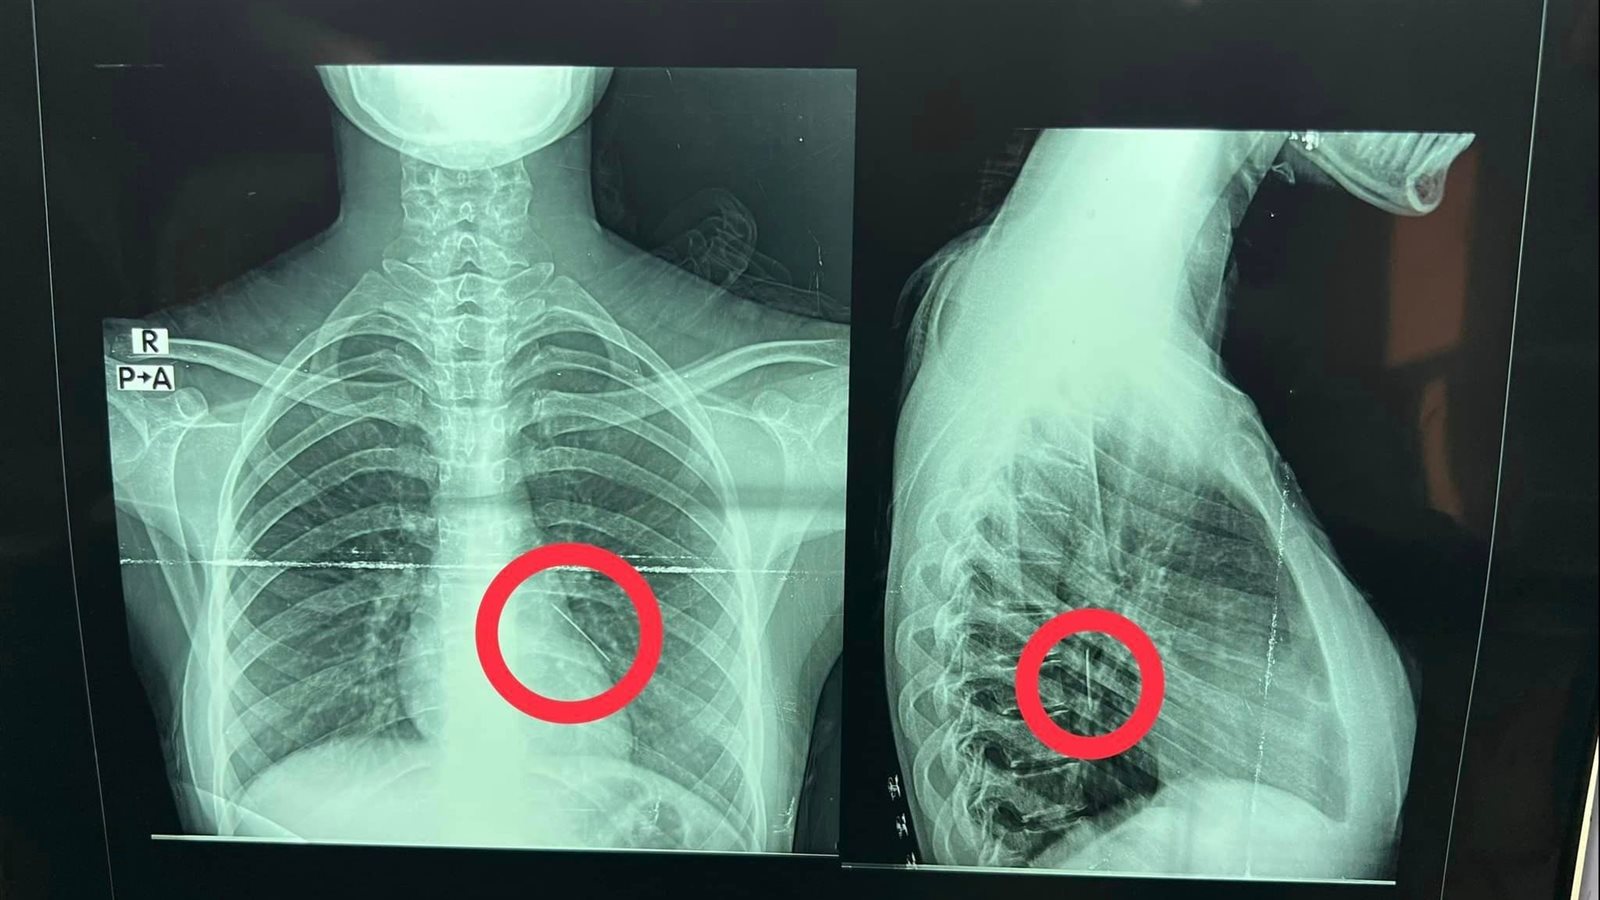

نجح فريق جراحى بقسم جراحة القلب والصدر بمستشفى بنها الجامعي بمحافظة القليوبية، في إنقاذ حياة فتاة تبلغ من العمر حوالي 18 سنة، ابتلعت "دبوس طرحة" عن طريق الخطأ أثناء لبسها للطرحة، واستقر بالرئة، تم عمل جراحة منظار شعب هوائية واستخراج الدبوس دون الحاجة لفتح صدر المريضة.

وكشفت مستشفى بنها الجامعي، بقيادة الدكتور عمرو الدخاخني المدير التنفيذي لمستشفى بنها الجامعي، أنه تم إجراء عملية طارئة لاستخراج دبوس طرحة من القصبة الهوائية اليسرى لفتاة تبلغ من العمر 18 عام، ابتلعته عن طريق الخطأ أثناء لبسها للطرحة ونزل في الرئة.

وبدوره، قال الدكتور محمد الجزار استشاري جراحة القلب والصدر بالمستشفى، أنه تم على الفور إدخال الفتاة لقسم جراحة القلب والصدر، وتم إجراء عملية منظار شعب هوائية صلب، وتم استخراج الدبوس دون الحاجة لفتح صدر المريضة